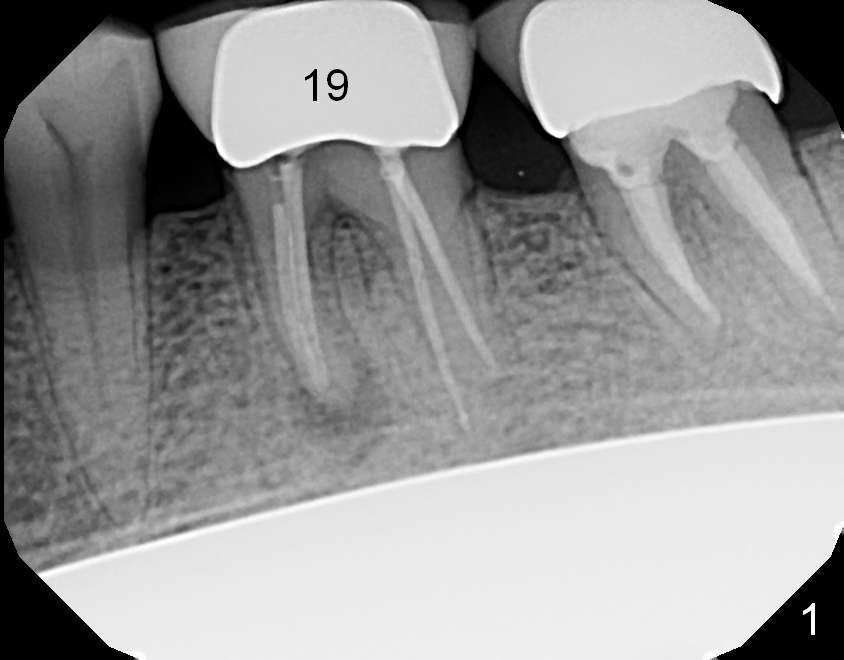

A 69-year-old man has pain in the tooth #19 (Fig.1). When a rubber dam clamp is placed for retreatment, the crown falls out (Fig2). Due to short clinical crown, the tooth is deemed non-salvageable. Fig.3 is an illustration after extraction. It seems that the septum is wide at the base. Measure socket depth. An osteotomy will be 1 mm longer than the socket depth (Fig.4). The osteotomy is initiated in the middle of the septum 14 mm deep. Insert a shortest parallel pin for occlusal check and a 14 mm long parallel pin for X-ray. Change trajectory if needed. A 5x14 mm tissue-level implant or 12 mm bone-level implant will be placed to prove that a short implant can achieve primary stability mainly by engagement into the septal struts and ~ 1 mm into apical new bone. With 2 roots distally, the position of the immediate implant will be affected?